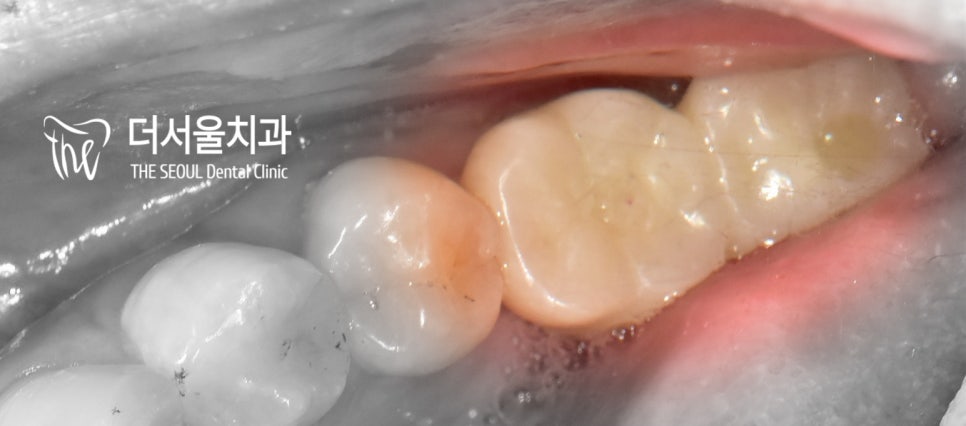

드디어 20대 임플란트 환자의

최종보철을 올려드릴 날이 밝았습니다.

과연 자연치 형태, 색조 그대로

재현이 잘 되었을까요?

지르코니아로 제작된 크라운을 올려드린 모습입니다.

교합은 물론이며 주변에 있는 인접치들과

잘 어울리고 있는 모습이죠~?